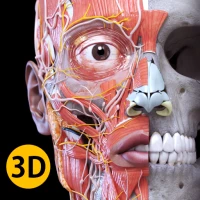

"Anatomy 3D Atlas" allows you to study human anatomy in an easy and interactive way.

Through a simple and intuitive interface it is possible to observe every anatomical structure from any angle.

The anatomical 3D models are particularly detailed and with textures up to 4k resolution.

"Anatomy - 3D Atlas" is an application aimed at medical students, doctors, physiotherapists, paramedics, nurses, athletic trainers and in anyone interested in deepening their knowledge of human anatomy.

This app is a fantastic tool to complement classic human anatomy books.

ANATOMICAL 3D MODELS

• Musculoskeletal system

• Cardiovascular system

• Nervous system

• Respiratory System

• Digestive System

• Urogenital system (male and female)

• Endocrine system

• Lymphatic system

• Eye and ear system